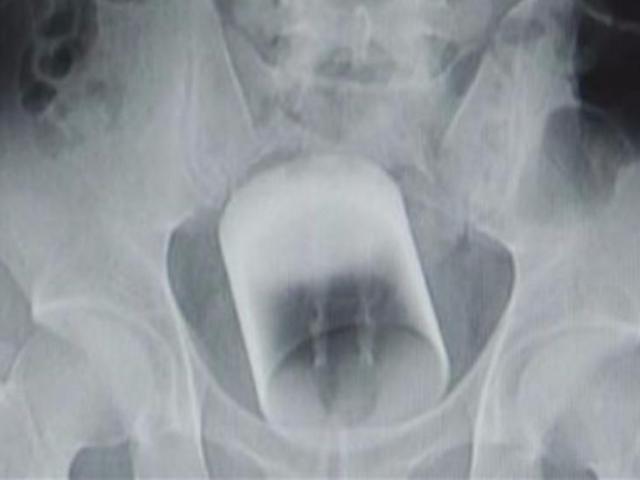

Cảnh sát phát hiện người đàn ông giấu 6 điện thoại trong hậu môn.

Nhưng trước khi người đàn ông này có cơ hội gặp các bạn tù, cảnh sát Israel đã kiểm tra toàn thân và phát hiện người đàn ông giấu 6 chiếc điện thoại trong hậu môn.

6 chiếc điện thoại lần lượt được lấy ra ngoài thông qua đường ruột. Cảnh sát hiện đang truy lùng đường dây đưa điện thoại vào nhà tù để các tù nhân có thể liên lạc ra ngoài.